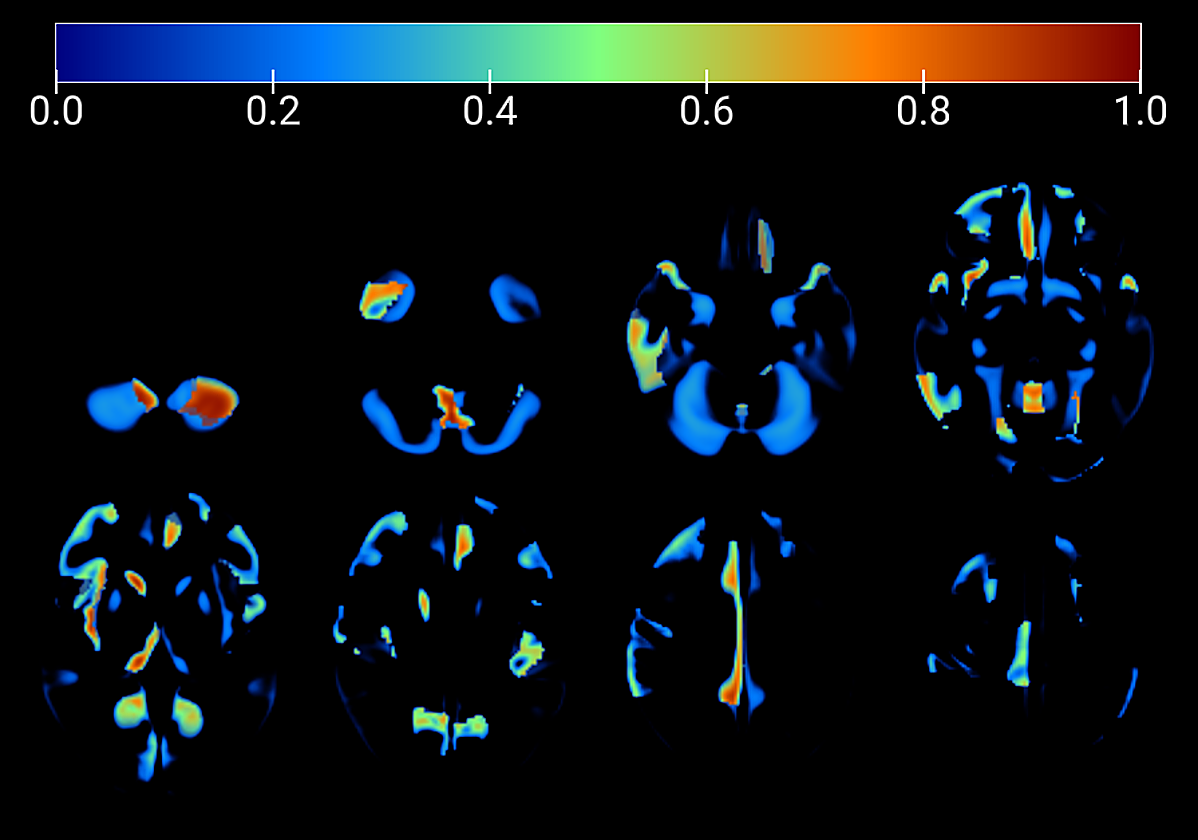

Las técnicas de imagen son claves para estudiar el cerebro de personas con demencias, síndrome de Down y autismo

El profesor Juan Manuel Górriz explica que las técnicas médicas de imagen son fundamentales en la evaluación de estas alteraciones y su relación entre sí. «A través de técnicas como el TACo la resonancia magnética podemos extraer información del cerebro sin abrir el cerebro», explica. La enfermedad de Parkinson y los trastornos del espectro autista son otras condiciones que se pueden estudiar mediante estas técnicas.